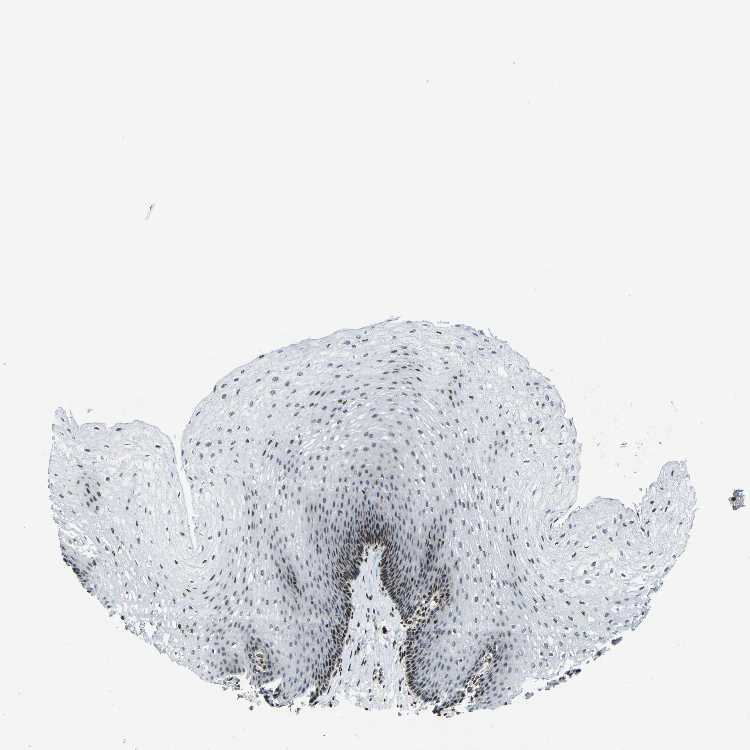

TISSUE PRIMARY DATA ESOPHAGUS Show tissue menu

ESOPHAGUS - Antibody stainingi

Antibody staining in the annotated cell types in the current human tissue is reported as not detected, low, medium, or high, based on conventional immunohistochemistry profiling in selected tissues. This score is based on the combination of the staining intensity and fraction of stained cells.

Each image is clickable and will lead to virtual microscopy that enables deeper exploration of all samples and also displays staining intensity scores, fraction scores and subcellular localization as well as patient and tissue information for each sample.

Antibody HPA068431Antibody CAB012235

Squamous epithelial cells Not detectedLow